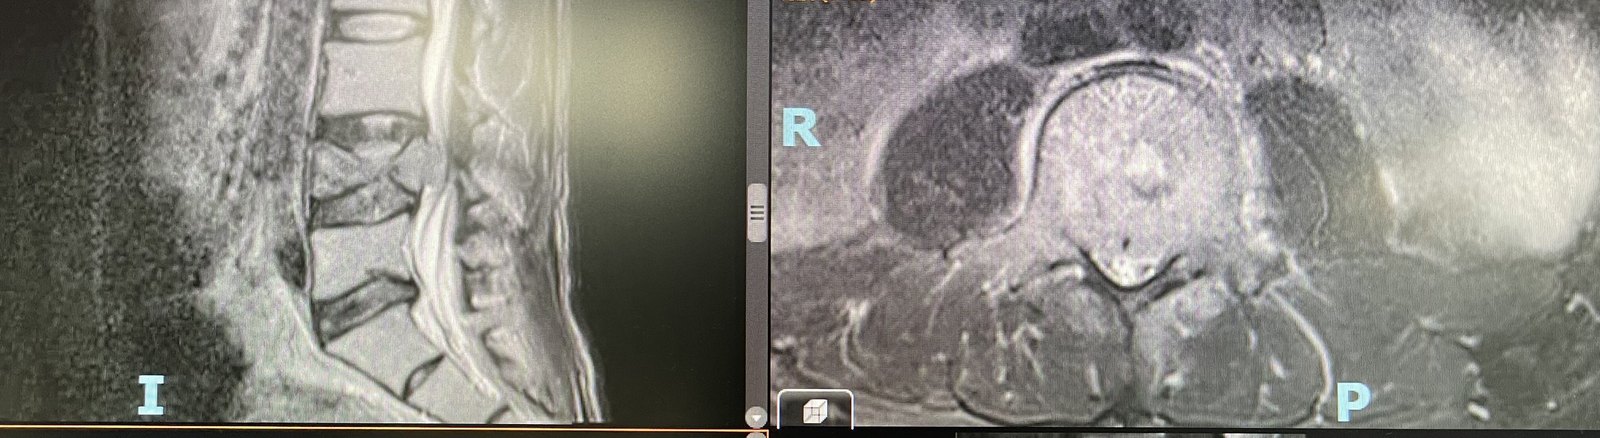

患者中年男性,消化道恶性肿瘤术后5年,胸腰椎转移。患者就诊主要症状:胸腰背部疼痛、腰骶交界区为重,夜间明显,弯腰受限,双侧小腿外侧麻木;体查:T10-11、L4-S1节段压痛、叩痛阳性,疼痛可放射至右侧小腿及足背,双侧L5以下感觉平面减退,右侧小腿及踝关节拮抗肌肌力IV级,余未及异常。

影像学检查如下:

术前一天行介入下栓塞;次日行T11、L4节段分离手术,胸椎短节段固定(移动窗、小切口),腰椎长节段固定(间隙固定),术中出血量不足1000ml。